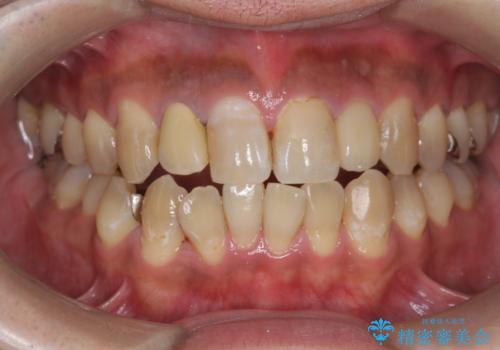

PMTCでコーヒーによる着色を除去。

- コーヒーを毎日飲むため、歯の表面についた着色をとりたいと来院されました。

歯の着色だけでなく、汚れもとれ歯の表面がツルツルになったと

喜んでいただけました。